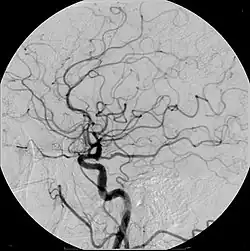

![]() Example of iodine-based contrast in cerebral angiography | |

Digital subtraction angiography (DSA) is a fluoroscopy technique used in interventional radiology to clearly visualize blood vessels in a bony or dense soft tissue environment. Images are produced using contrast medium by subtracting a "pre-contrast image" or mask from subsequent images, once the contrast medium has been introduced into a structure. Hence the term "digital subtraction angiography.[1][2] Subtraction angiography was first described in 1935 and in English sources in 1962 as a manual technique. Digital technology made DSA practical starting in the 1970s.[3][4]